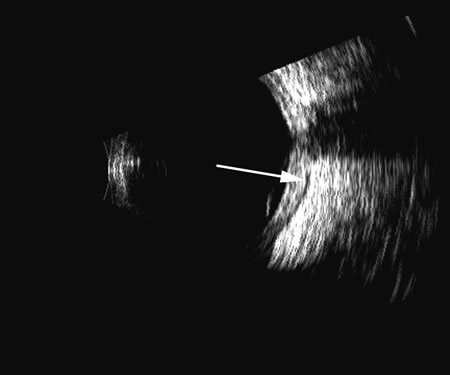

Vitreous foreign bodies are typically metal or glass objects, or intraocular lens implants. The ultrasound examination, with its better spatial resolution, is best performed following radiographic or computed tomography examinations in order to identify the location and number of foreign bodies. Ultrasonography is used to relate the position of a foreign body to the retina and lens and identify coexisting structural changes, such as retinal detachment. Metal and glass “absorb” or, more correctly, deflect sound, so that an anechoic area appears posterior to the foreign body. This area can act as an acoustic “pointer” to the foreign body (Fig. 18). A-scan or gray scale on B-scan shows a highly reflective surface of the foreign body. BBs and shotgun pellets often create a “ringing” artifact that can also act as a pointer leading to the foreign body.19 The foreign body can be easily demonstrated by lowering the gain; the foreign body remains, whereas other, less reflective tissue planes fade away due to a lower difference in acoustic impedance between tissues than metallic or glass foreign bodies. Most foreign materials have a higher density than the vitreous, and sound that passes through the foreign body may appear to move the succeeding surface forward because of the faster sound transit.

Fig. 18. A foreign body localized in the iris is easily imaged with high frequency. Characteristic trailing multiple echoes always point to the location of the body itself (arrow).